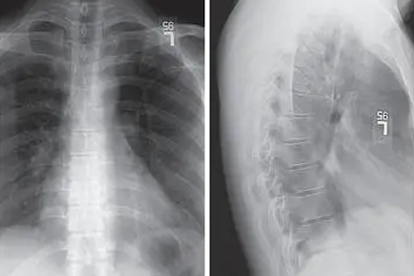

胚胎期椎体分节障碍导致半椎体、蝴蝶椎等结构异常。新生儿期可通过MRI确诊,20度以内畸形建议观察,40度以上需考虑后路脊柱融合术,术中采用椎弓根螺钉系统固定。

重度畸形可能压迫胸腔脏器,表现为呼吸困难、反复肺炎。需每半年评估肺功能,合并限制性通气障碍时,优先行胸廓成形术联合矫形手术,术后配合高频胸壁振荡排痰训练。